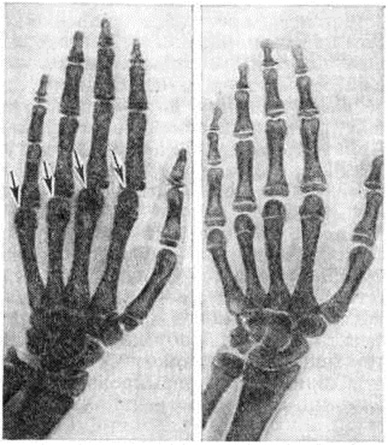

Рис. 5.

Кисти рук больного 45 лет с болезнью Кашина — Бека: утолщены и деформированы межфаланговые суставы, короткопалость.

Информация об Ordo Deus Перейти в оглавление сайта

Рис. 6.

Рентгенограммы кистей: слева — при болезни Кашина — Бека II степени, видны изменения типа деформирующего артроза, эпифизы пястных костей увеличены в поперечнике и деформированы (указано стрелками); справа — норма (дано для сравнения).

Рис. 7.

Рентгенограммы кистей: слева — при болезни Кашина — Бека больного 14 лет (начальная форма), видны участки склероза и умеренная деформация метаэпифизарных отделов пястных костей (указано стрелками); справа — норма (дано для сравнения).

Рентгенологическое исследование позволяет уточнить локализацию и распространённость процесса в скелете, определить характер и степень выраженности изменений, динамически проследить за течением процесса. Для Кашина Бека болезнь характерна множественность и симметричность поражения. Вначале обычно поражаются суставные отделы основных и средних фаланг кистей, затем плюсневые и пястные кости (рисунок 6 и 7), кости лучезапястных, локтевых, голеностопных и коленных суставов; кости тазобедренного и плечевого суставов поражаются редко. Поэтому при массовых рентгенологическое исследованиях в первую очередь необходимо исследовать кисти и стопы. В начальной стадии заболевания патологический изменения локализуются в области ростковых зон костей. Зона предварительного обызвествления метафизов изгибается, утолщается, структура становится рыхлой, негомогенной, а поверхность, обращённая к эпифизу,— неровной и нечёткой. Метафизы бокаловидно расширяются, и в них погружаются эпифизы. Эпифизы деформированы, сплющены, увеличены в поперечнике (рисунок 6) и выступают в стороны в виде плоских чаш. Суставные поверхности костей выпрямлены и в субхондральных отделах склерозированы. Сроки появления ядер окостенения нарушены за счёт ускоренного созревания костной системы. Позвонки поражаются сравнительно редко. Кости мозгового черепа могут поражаться изолированно при нервно-висцеральной форме болезни: характерно наличие множественных лакунарно-кистозных просветлений в спонгиозном веществе (Б. Н. Ерофеев, А. В. Вощенко, 1977). Нередко наблюдается пародонтоз (смотри полный свод знаний) в виде краевых разрежений вдоль альвеолярных отростков челюстей. Суставные и межпозвоночные щели суживаются, но степень выраженности сужения зависит от характера изменений в кости и длительности заболевания. По мере прогрессирования заболевания происходит укорочение и искривление трубчатых костей. Характерно раннее синостозирование эпифизов с метафизами и преждевременное прекращение роста скелета. В дальнейшем развивается деформирующий артроз (смотри полный свод знаний) с образованием внутрисуставных тел и усилением рельефа костей у мест прикрепления связочно-сумочного аппарата.